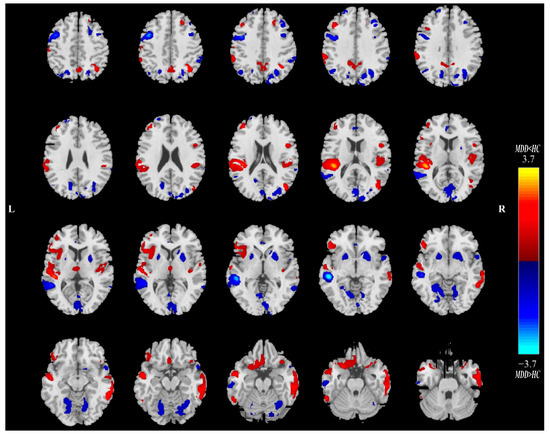

Twenty ICs for QSM and sMRI were estimated in this study. Intergroup statistics were applied using the two-sample t-test to analyze the mixing coefficients of each IC. As shown in Figure 2, the third independent component (IC03) can differentiate between the MDD and HC groups in terms of QSM and GMV. Meanwhile, there is a significant correlation between QSM_IC03 and GMV_IC03. Therefore, IC03 is the joint group-discriminative IC that we finally obtained. IC03 exhibited significant inter-group differences in QSM (** p = 0.0095) and GMV (** p = 0.0081) metrics, respectively (see Figure 2A,B). QSM_IC03 exhibited positive correlations with GMV_IC03 (r = 0.7111, **** p < 0.0001) (Figure 2C). These p values passed the FDR correction for multiple comparisons. Spatial maps of QSM_IC03 and GMV_IC03 were transformed into Z scores and are visualized at |Z| > 2 in Figure 3 and Figure 4. The mean mixing coefficients were adjusted as HC subjects > MDD participants for QSM and GMV (Figure 2A,B), meaning the red brain regions (Z > 0) represent areas where QSM and GMV values of the HC group were higher than the MDD group. In contrast, blue brain regions (Z < 0) indicate areas where QSM and GMV values of the MDD group were higher than the HC group (Figure 3 and Figure 4).

Figure 4.

The spatial maps for GMV_IC03 visualized at |Z| > 2, where the red brain regions (Z > 0) mean higher GMV values in HC subjects than MDD participants, and the blue brain regions (Z < 0) indicate higher GMV values in MDD subjects than HC participants.; MDD = major depressive disorder; HC = healthy control.

Overall, lower QSM values were observed in the bilateral CN, GP, middle frontal gyrus and other regions of MDD patients in the spatial map of QSM_IC03. For bilateral PU, THA, anterior cingulate cortex, superior temporal gyrus and parahippocampal gyrus, etc., the QSM values of MDD in these regions are greater than those of HCs (Figure 3). As for the GMV_IC03 (Figure 4), the GMV values of anterior cingulate cortex, bilateral PU, supramarginal gyrus and lingual gyrus in MDD patients increased compared with the HCs. In the right insula, bilateral superior temporal gyrus, right gyrus rectus, orbital gyrus and THA, the GMV values of MDD patients were lower than those of HCs.